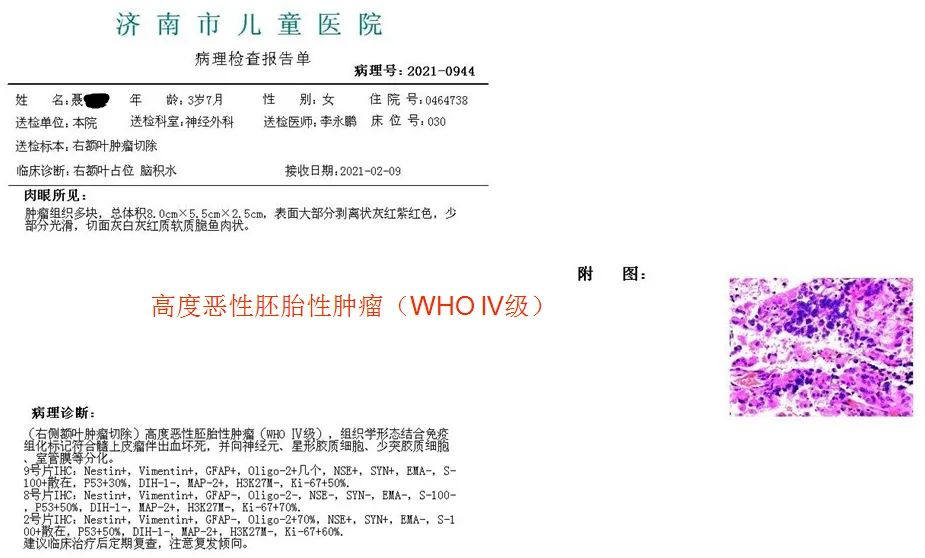

术后病理

下一步治疗:

1. 化疗

2. 放疗

3. 分子基因检测